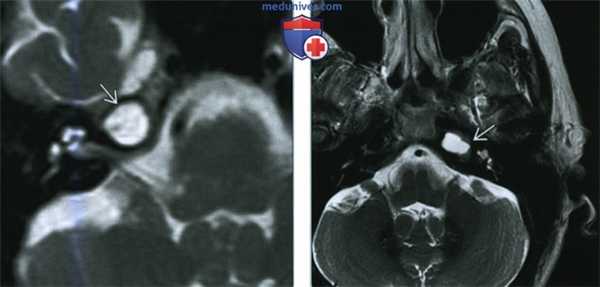

(Слева) При аксиальной МРТ Т2ВИ определяется подозрительный гиперинтенсивный участок в вершине пирамиды слева (МРТ выполнена по поводу потери сознания у пациента). Рентгенолог предположил холестериновую гранулему и назначил КТ височных костей для дообследования.

(Справа) При аксиальной КТ в костном окне у этого же пациента определяется снижение пневматизации ячеек в вершине пирамиды слева без признаков вздутия или разрушения трабекул. Было сделано заключение о «запертой» жидкости, не требующей наблюдения.